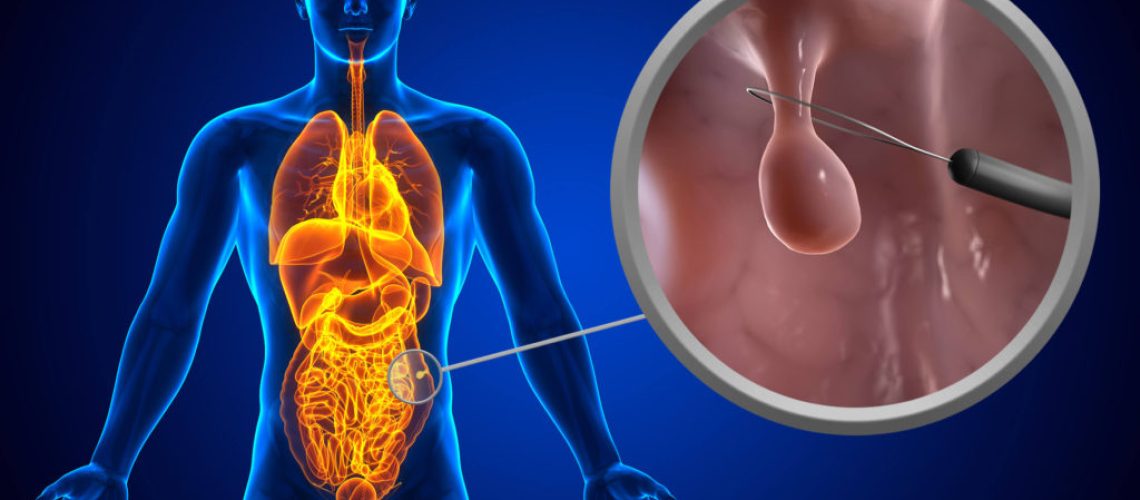

پولیپکتومی یکی از روشهای جراحی است که در آن پولیپهای موجود در سیستم گوارش و کبد برداشته میشوند. این جراحی برای درمان برخی از بیماریهای مرتبط با پولیپها مورد استفاده قرار میگیرد. برخی از موارد معمول برای اجرای پولیپکتومی شامل پولیپهای بزرگ، پولیپهای خطرناک مانند پولیپهای حاوی سلولهای آب بران و پولیپهایی که علائمی مانند خونریزی دارند، است. این جراحی به عنوان یک روش درمانی مناسب برای پولیپهای گوارشی و کبدی شناخته شده است و به بیماران کمک میکند تا بهبود خود را تجربه و از علائم ناراحت کننده پولیپها رها شوند. با انجام پولیپکتومی، پتانسیل برای رشد پولیپهای بیشتر در آینده کاهش مییابد و بیمار میتواند به طور کامل به سلامتی خود بازگردد.

پیش از جراحی یک سری تستها و بررسیها برای تشخیص و بررسی پولیپهای گوارشی صورت میگیرد. این بررسیها شامل آندوسکوپی (معاینه درونی سیستم گوارشی با استفاده از یک لوله نازک انعطافپذیر که دارای دوربین است) و بیوپسی (برداشتن نمونههای بافتی برای آزمایش) است.

جراحی

در مرحله جراحی، پولیپ از داخل گوارش یا کبد برداشته میشود. این جراحی میتواند به صورت باز یا به صورت لاپاراسکوپیک (استفاده از لوله نازکی که دوربین و ابزار جراحی را به داخل گوارش یا کبد میبرد) انجام شود. هدف از جراحی برداشتن پولیپ، برطرف کردن مشکل و جلوگیری از پیشرفت بیشتر پولیپ و تغییرات آن به سرطان است.